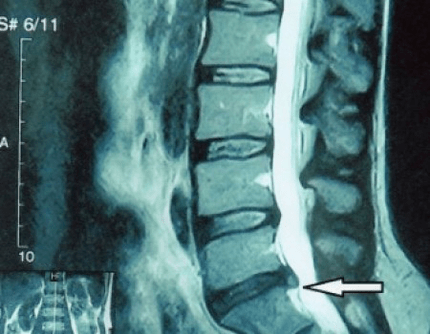

protrusion of a spinal disc on an MRI

Since the discs themselves can only be visualized using CT or MRI, MRI and X-ray CT are indicated to clarify the internal structure of the cartilage and formations such as protrusions and hernias.Thus, with the help of these methods, the diagnosis is made accurately, and the tomography result is an indication, and even a topical guide, for the surgical treatment of a hernia in the neurosurgery sector.